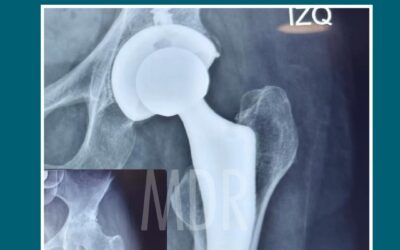

Caso de Éxito: Paciente con Prótesis de Cadera

Volver a moverte sin dolor también es calidad de vida